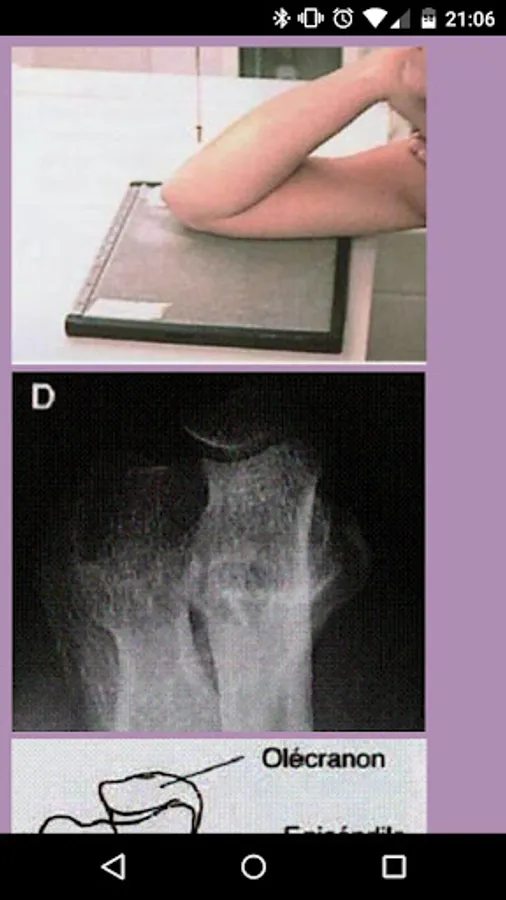

Manual radiologic projections to quickly access the most common projections gradually be adding more projections rx.

RADIOLOGY MANUAL PRO Screenshots